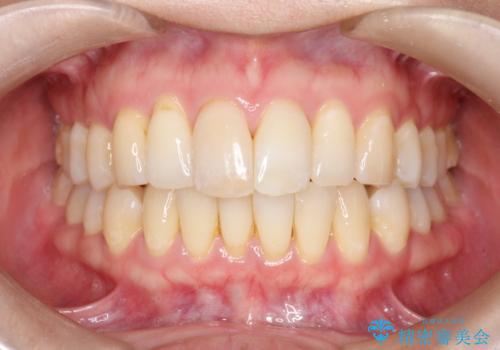

再矯正をインビザラインで目立たず手軽に

- 以前矯正をしていたが、わずかに後戻りをしてしまったのを主訴に来院されました。

装置はなるべくつけたくないとのことで、インビザラインにて治療することとなりました。

以前ワイヤー矯正をされていた方は、装置をつけての再矯正を希望されない方もいます。

その場合にインビザラインをお勧めさせていただいております。

後戻りがわずかな場合は、期間も短くて済む場合があります。